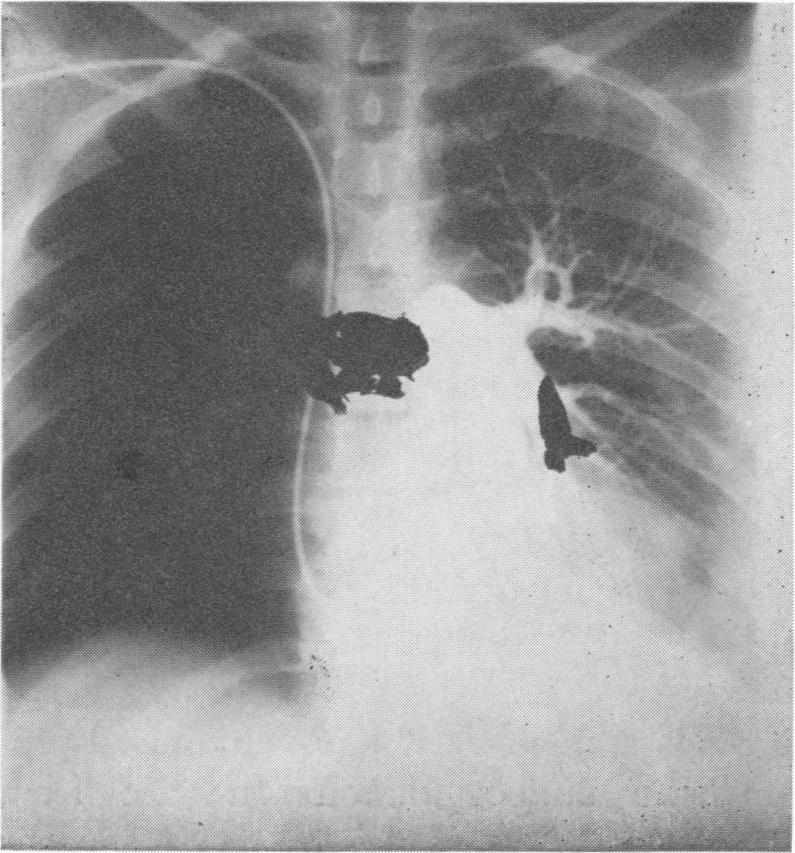

Pulmonary embolism revisited.

Ann Surg. 1969 Jun;169(6):947-53. doi: 10.1097/00000658-196906000-00014.